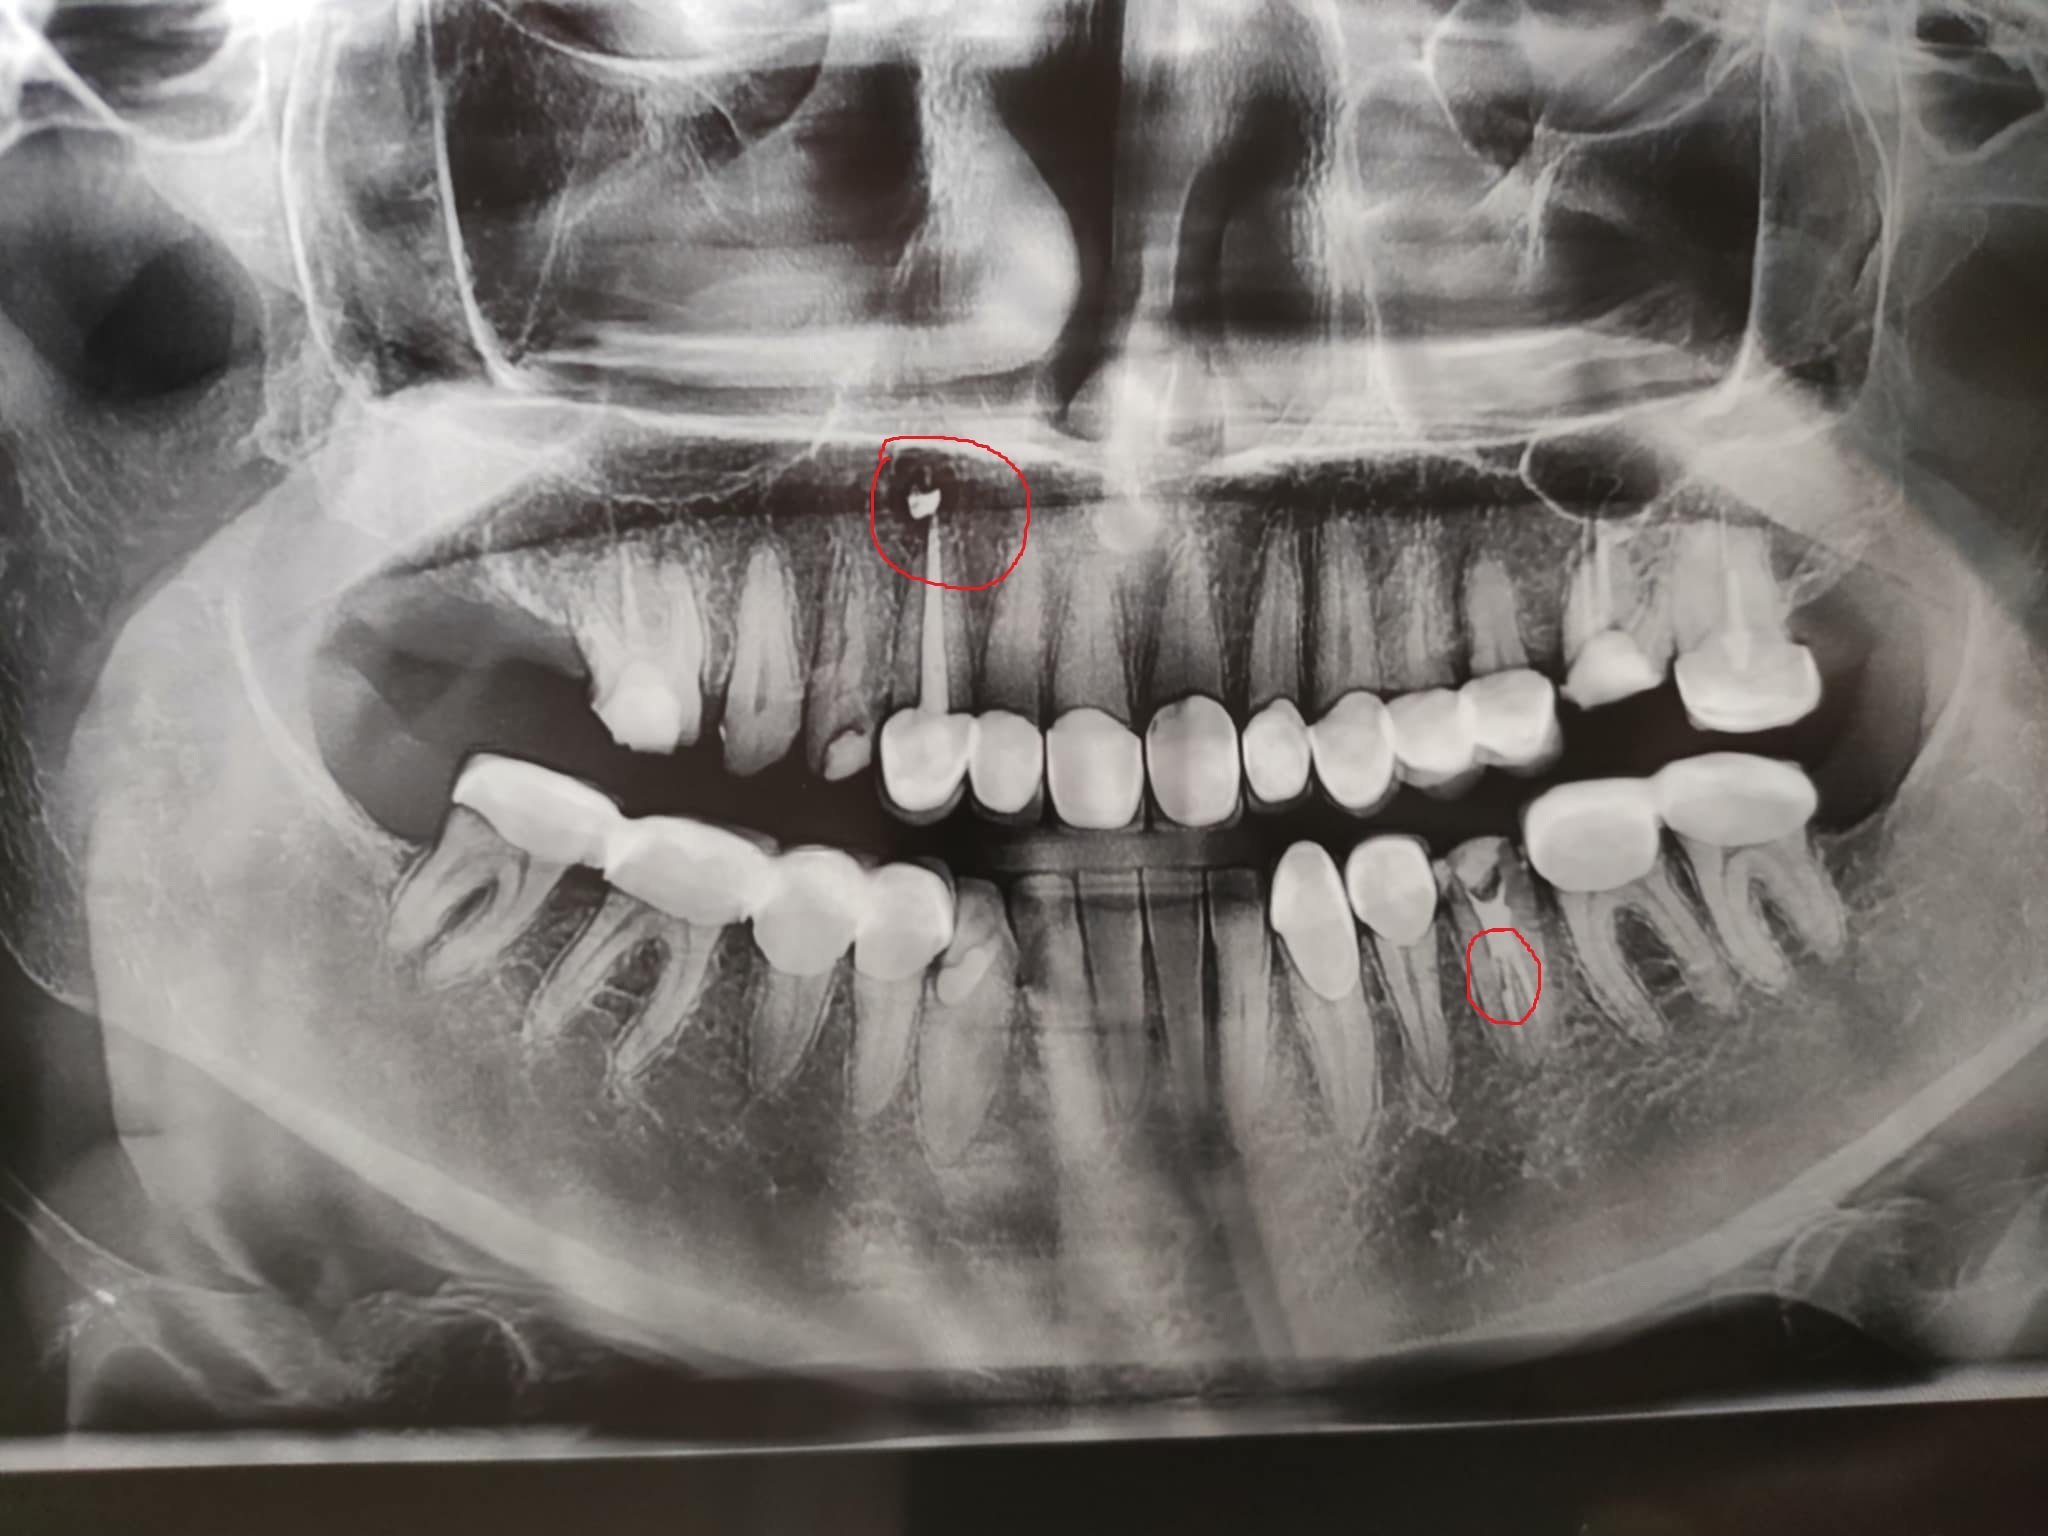

Днес ми запълниха канала на лекуван зъб и отидох за снимка до рентгена и като се върнах докторът беше взел по спешност да оперира ретиниран мъдрец. Операцията на пациента се забави и трябваше да тръгвам за работа и не изчаках. Следващият ми час е другата седмица. Прикачам снимка и съм отбелязала нещата, които ме притесняват-защо на горния кучешки зъб има бяла топчица над канала и на долния зъб, който съшо съм оградила, ми се струва , че имам счупен корен или някакво прекъсване в корена. Много съм притеснена, защото съм опатила от зъби. Ще съм благодарна, ако ми се даде и малка насока, поне да зная какво адекватно да попитам зъболекаря си  следващия път. Освен това усещам болка при дъвчене и неразположение. Имам и лека температура. Благодаря предварително.